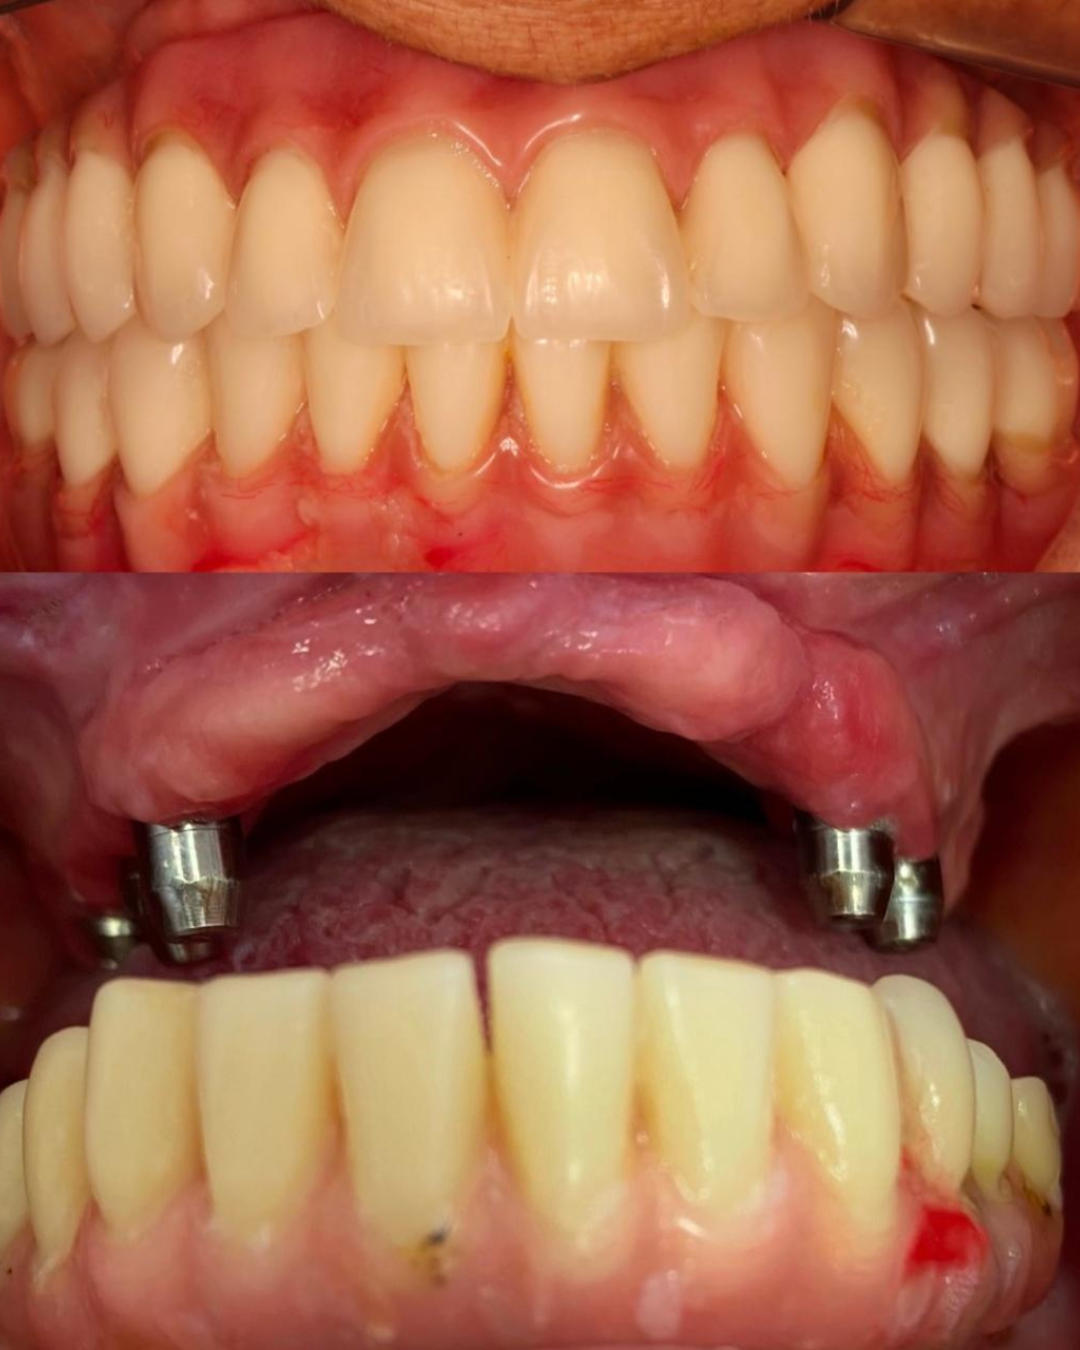

Soluções estéticas como implantes e próteses para um sorriso completo.